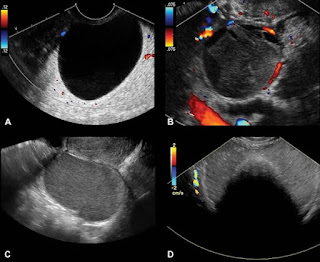

Not all benign ovarian cysts require surgery. In fact, many of these cysts can resolve on their own, particularly if they are small and asymptomatic. Your doctor will likely monitor the cyst over time with follow-up ultrasounds to see if it shrinks or disappears. If the cyst is asymptomatic and doesn't grow, it may not require any intervention at all.

Surgery may be recommended if the cyst is large, causing symptoms, or shows signs of complexity (such as irregular shape or solid areas). The decision to operate is usually made to alleviate symptoms, prevent complications like rupture or torsion, or to rule out any potential malignancy.